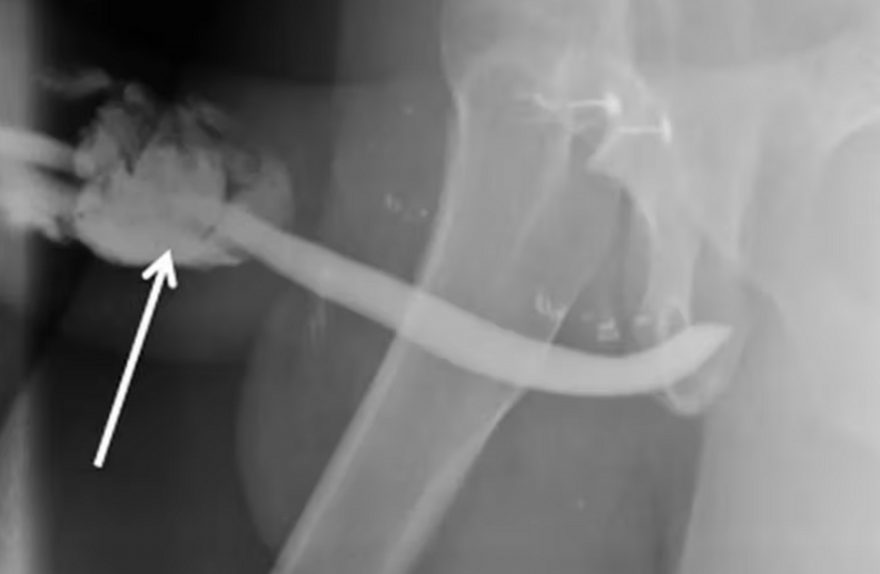

Inusitado: Homem fratura pênis em três lugares durante relação

sexual.

Um homem de 36 anos teve três fraturas no pênis enquanto tinha relação sexual. O episódio aconteceu na Tanzânia e foi considerado incomum por médicos que trataram dos ferimentos.

Segundo informações do Journal of Surgery Case Reports, o homem relatou que estava deitado na cama e a parceira estava por cima dele. Durante a movimentação no ato sexual, ele tentou reinserir o pênis na vagina da mulher e, neste momento, ouviu um barulho de estalo. Esta posição, segundo médicos, pode ser perigosa e causar dano ao pênis se feita sem cautela.

Em seguida, o homem perdeu a ereção. Ele também notou que o pênis começou a inchar e que havia sangue escorrendo pela uretra. Cinco horas depois, ele se direcionou para o hospital, onde foi identificado que o choque com o períneo causou a quebra do órgão.

De acordo com o jornal científico, houve fraturas em ambos corpos cavernosos do pênis e também no corpo esponjoso – parte que protege a uretra.

A fratura peniana acontece quando o órgão é forçado a dobrar de forma excessiva enquanto está ereto, o que pode acontecer durante o sexo ou pela masturbação. Caso não seja tratada corretamente (algumas delas requerem cirurgia), pode levar o homem a ter cicatrizes permanentes ou até disfunção erétil.